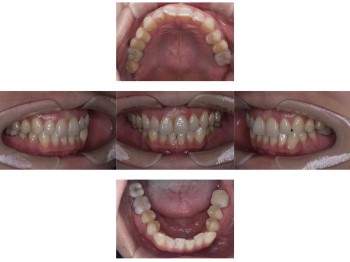

口腔内写真

- Befor

- After

| 年齢 | 50代・男性 |

|---|---|

| 主訴 | 左上7番 左下5番7番 |

| 治療内容 | ・インプラント埋入 ※1:GBR(骨造成)・・・骨再生誘導法。骨の高さや厚みを人工骨や人工膜などを使用し再生する方法 |

| 治療費 | 合計:1,809,500円(税込) ■内訳 ・左上7番 ・左下5番7番 |

| 治療期間 | 左上7番約1年 左下5番7番約10ヵ月 |

| 治療方針 | 左上7番は昔他院で被せものをしており、被せものの中が歯ぐきの中まで虫歯になっていたため抜歯せざるを得ない状態だった。抜歯と同時に骨造成を行い、骨が出来るまで4ヵ月待ってからインプラントを埋入した。 ※2ポンティック・・・歯のない部分を補うダミーの歯。 |

| 担当者所見 | 元々金属の被せものが多く入っていたため、2次カリエス※3が多かった。今回は金属ではなく、ジルコニアを使用し、2次カリエスにならないよう、患者様にはブラッシング指導とメンテナンスの重要性をお伝えした。 ※3二次カリエス・・・詰め物や被せものを入れた歯が虫歯になること。 |